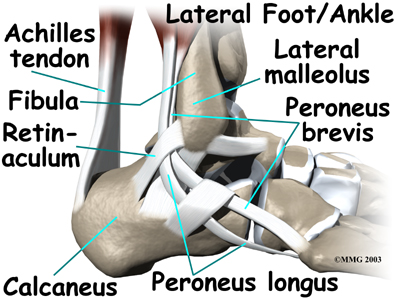

The anterior tibial tendon allows us to raise the foot. Two tendons run behind the outer bump of the ankle (the lateral malleolus). These two tendons, called the peroneals, help turn the foot down and out.

- The peroneals (peroneus longus and peroneus brevis) on the outside edge of the ankle and foot bend the ankle down and out.